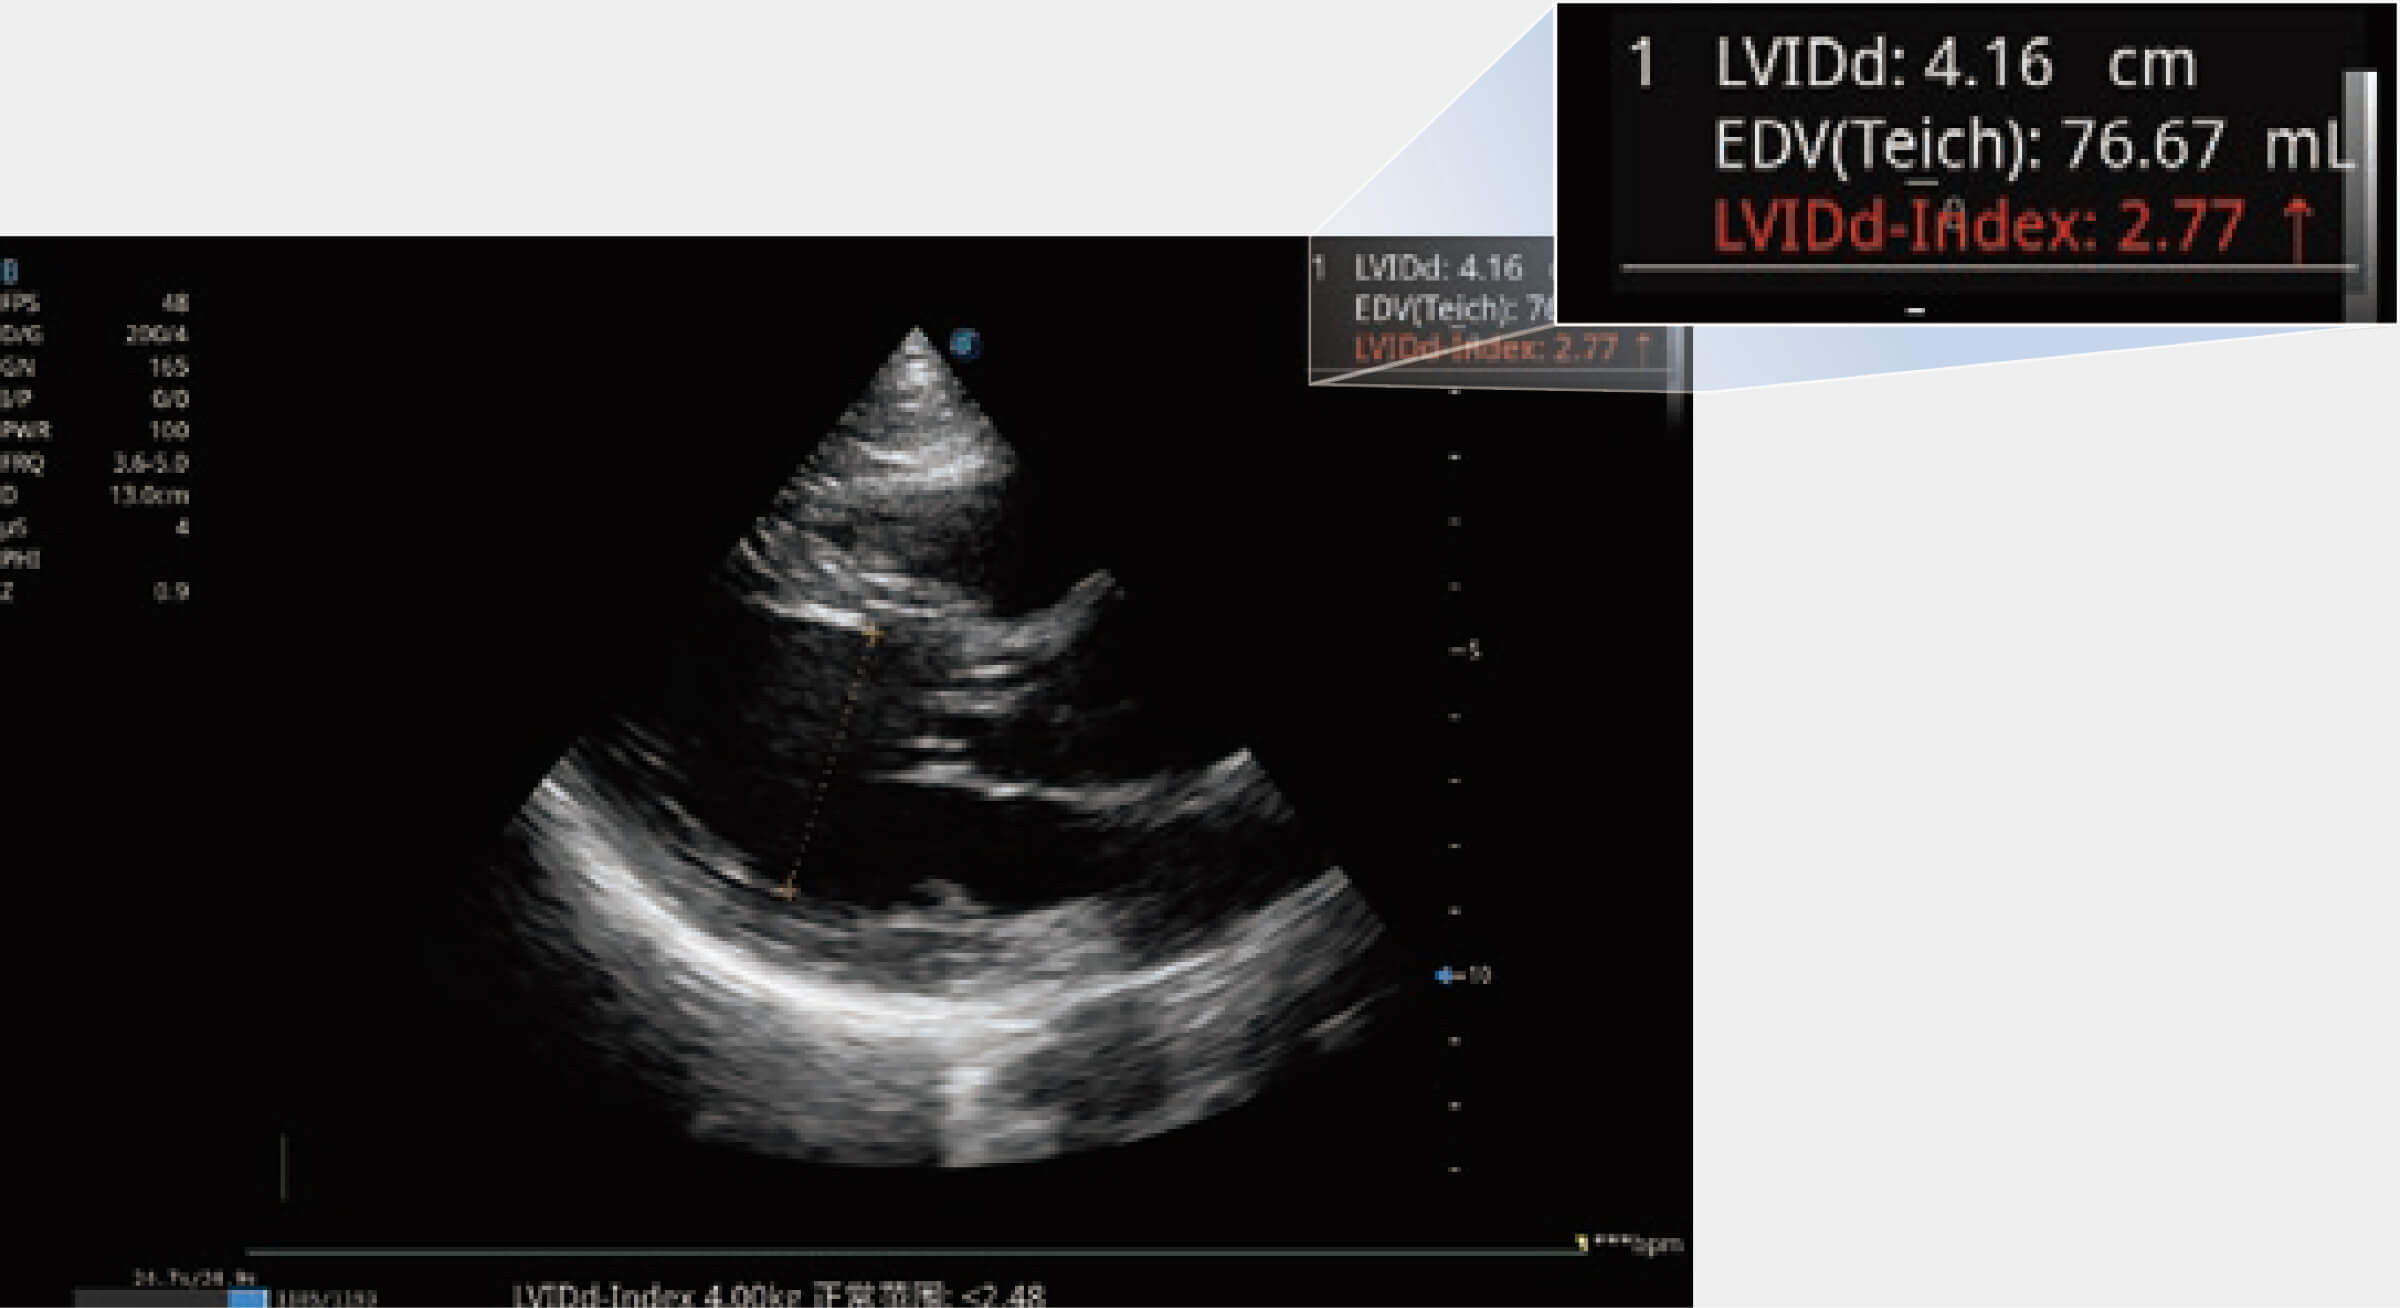

能够基于左心室壁追踪和辛普森法,自动计算射血分数,支持多个可移动点描迹,与手动测量相比,极大节省了动物医生的时间和精力。

ProPet 80 专为动物医生设计,对不同的动物体型和生理结构作出了针对性的优化。通过动物影像专用软件,可满足个性化的应用需求,帮助动物医生获得更精确的诊断数据。

为精细结构及组织边缘提供高清晰度的图像和更大的成像视野。帮助减轻医生的用眼疲劳,快速精准获得测量的数据。

当心脏测量结果超出正常范围时,可实时预警提示动物医生,减少疾病漏诊概率。

能够基于左心室壁追踪和辛普森法,自动计算射血分数,支持多个可移动点描迹,与手动测量相比,极大节省了动物医生的时间和精力。